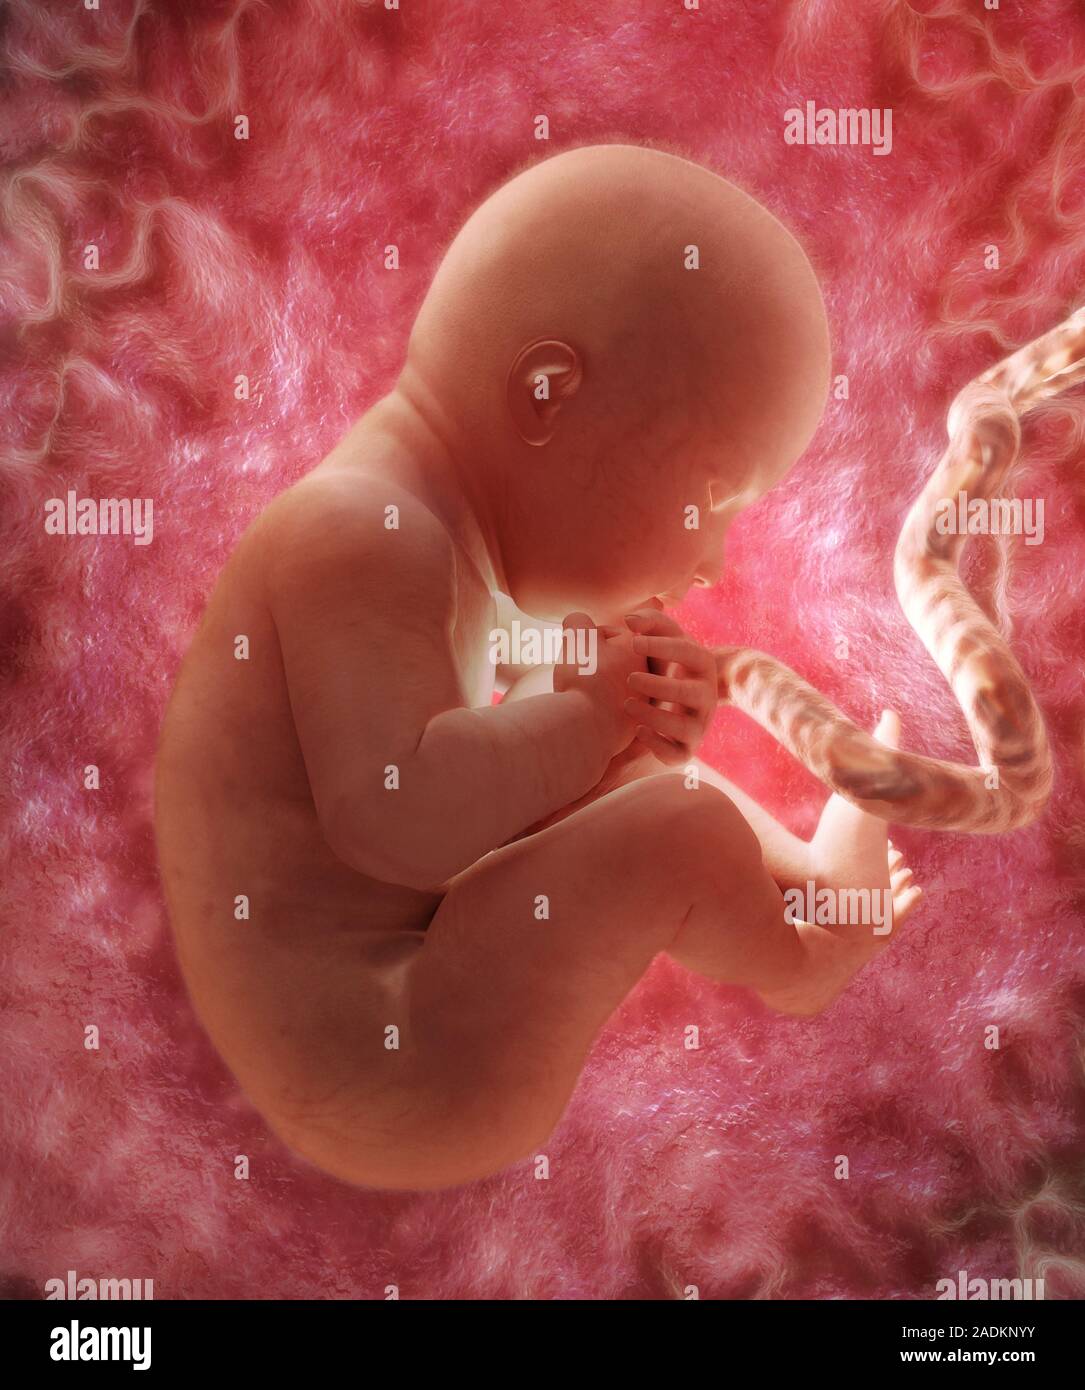

Фотография Плода В Животе

Фотография Плода В Животе 113 фотографий